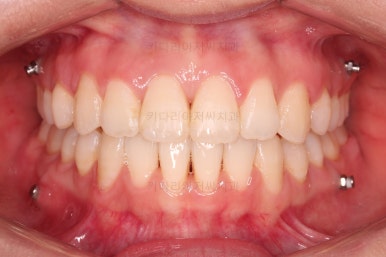

부산교정잘하는치과 초진 시 입안의 모습입ㄴ디ㅏ.

맞물림은 크게 나쁜 편은 아니었고요.

앞니 쪽이 위아래가 다 삐뚤고, 위에 작은 앞니 하나가 거꾸로 물리는 상태였습니다.

거꾸로 물리는 상황에서 특히 아래 앞니는 점점 잇몸이 꺼지는 증상이 생기면서 장기적인 치아의 수명에 영향을 주게 됩니다.

종료 시 사진입니다.

중앙선, 교합, 치아배열 모습 모두 양호해졌습니다.